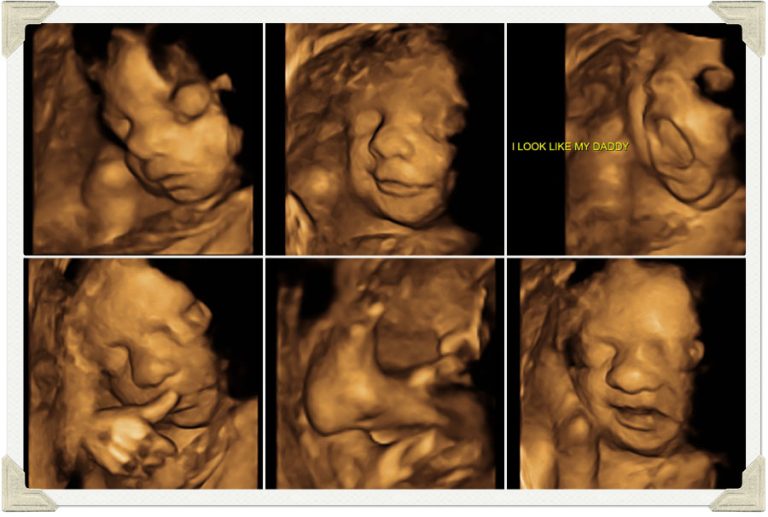

Važno je naglasiti da standardni ultrazvučni pregled ostaje nezamjenjiv dio savremene kontrole trudnoće. Sve više, 3D/4D analiza ploda postaje odlična dopuna uobičajenom pregledu, a kod sumnje na neke anomalije – naročito lica i ekstremiteta, sa šakama i stopalima, ovakav postupak je praktično metod izbora.

Poliklinika Sunce Agram pacijenticama nudi preglede najsavremenijim 4D ultrazvučnim aparatima. 4D razlikuje se od 3D prikaza utoliko jer omogućuje prikaz slike u stvarnom vremenu te samim time i bolji uvid u dinamiku i stanje ploda.

Najbolji kvalitet prikaza je od 26 do 34 nedjelje trudnoće. Kod sumnji na malformacije ploda pregled se radi i ranije.

4. 4D uzv pregledom vidimo bebino ponašanje, kako se smije, zijeva, mršti, i to kod roditelja budi posebne osjećaje, a ginekologu otkriva važne podatke o djetetovu razvoju. Koji su to parametri koje ginekolog gleda ovim pregledom?

Ova vrsta ultrazvuka pruža kvalitetu sa foto detaljima i suverena je u otkrivanju nekih malformacija ploda i njihovog izuzetno vjerodostojnog prikazivanja. 3D/ 4D koristi iste ultrazvučne talase kao i konvecionalni 2D samo što procesor aparata rekonstruiše serije tankih 2D snimaka i daje nam sliku u tri dimenzije odnosno ukoliko dobijamo sliku u realnom vremenu to nazivamo 4D ultrazvukom. Mi na Poliklinici prvo radimo standardni ultrazvučni pregled koji nam daje najviše informacija a poslije toga 3D/4D UZ slike i klipove možemo smatrati kao bonus. Gledanje bebice u stvarnom vremenu, sa svim detaljima pruža roditeljima osjećaj sigurnosti da je sa bebicom sve u redu i da se pravilno. Sam 4D UZ radi “ zabave“ ili određivanja spola bebice ne praktikujemo u svakodnevnom radu ali istovremeno, kako je riječ o bezbjednom pregledu, ne mogu da roditeljima uskratim jedno lijepo iskustvo.